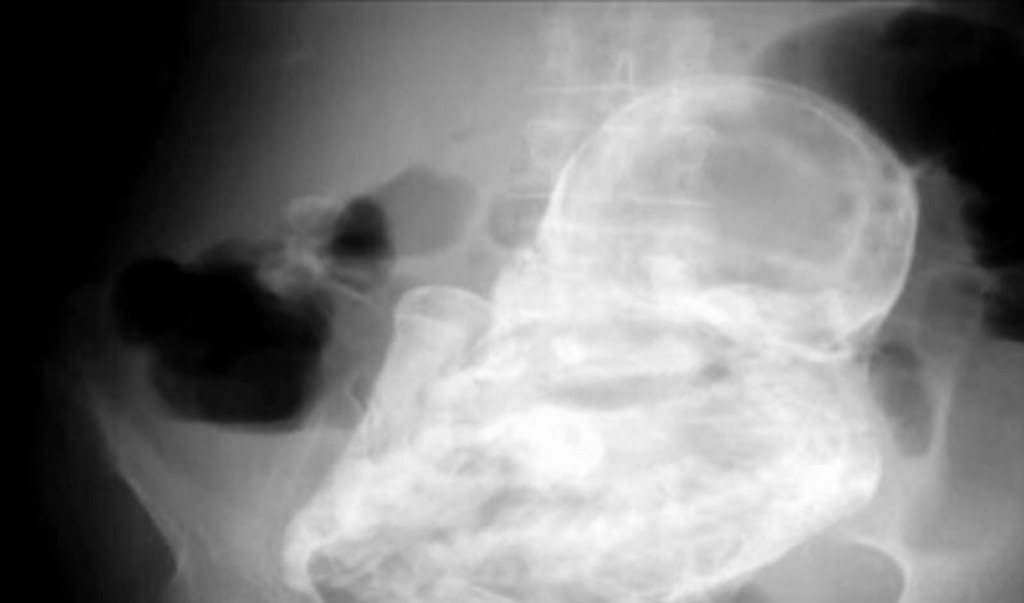

S naozaj nezvyčajným prípadom sa stretli lekári v kolumbijskej nemocnici v Bogote. Na pohotovosť prišla 82-ročná dôchodkyňa s bolesťami brucha. Odborníci si najskôr mysleli, že sú to žlčové kamene, ale skutočná príčina bolesti ich šokovala.

Lekár, ktorý ženu vyšetroval, si všimol v jej brušnej dutine niečo neobvyklé. Pacientke urobili ultrazvuk, ktorý ale nič neodhalil.

Zdroj: Reuters

Röntgenové vyšetrenie ukázalo pravého vinníka. Lekári sa ale domnievali, že ide o nádor. Neskôr zistili, že to bol kalcifikovaný plod dieťaťa.